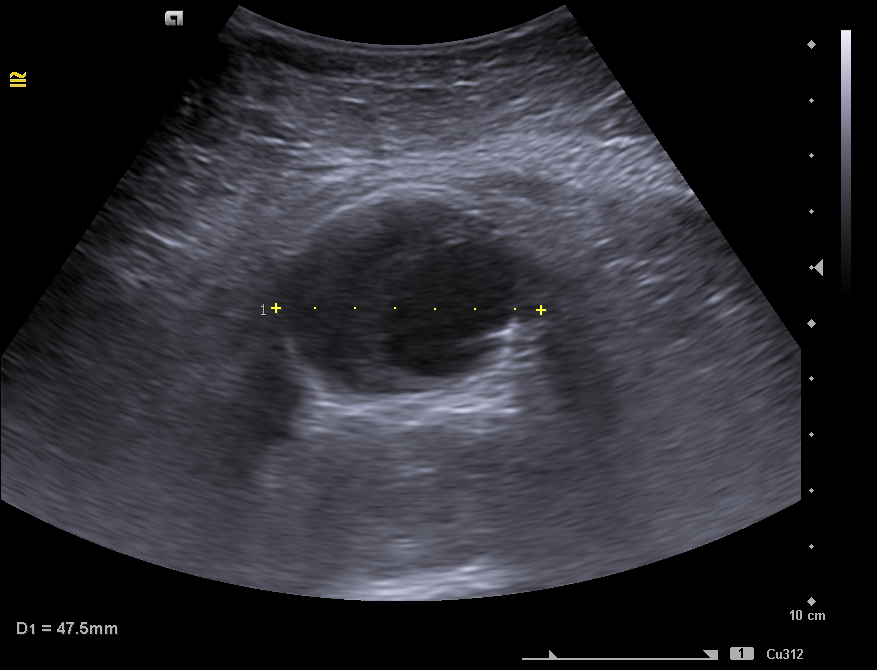

En la ecografía clínica se observa la aorta abdominal con calibre aumentado de tamaño (46 x 41 mm de diámetro), trombo mural interior y luz del vaso de 20 x 27 mm compatible con aneurisma de aorta abdominal fusiforme que se extiende hasta bifurcación aortoilíaca. Arterias ilíacas comunes sin datos de afectación.